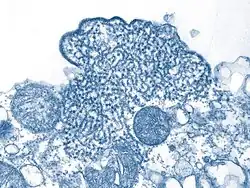

Das Nipah-Virus (NiV, auch NIPV, Spezies Henipavirus nipahense) ist ein Virus aus der Familie Paramyxoviridae,[3][4] das beim Menschen eine häufig tödlich verlaufende Gehirnentzündung (Enzephalitis) auslösen kann. Das Nipah-Virus tritt insbesondere in Südasien und Südostasien auf und kann durch Kontakt mit Körperflüssigkeiten und -ausscheidungen infizierter Tiere, Menschen oder Reservoirwirte oder dem Verzehr von kontaminierten Lebensmitteln übertragen werden. Reservoirwirte sind fruchtfressende Flughunde der Gattung Pteropus, die in Süd- und Südostasien sowie auf Madagaskar vorkommen. Diese Flughunde scheiden das Virus z. B. über Urin und Speichel aus und übertragen es in der Regel auf andere Tiere (insbesondere Schweine), die es auf den Menschen weiterübertragen.[5]

Das Nipah-Virus bildet zusammen mit dem eng verwandten Hendra-Virus die Gattung Henipavirus in der Familie der Paramyxoviridae. Es wurde erstmals 1999 im Zuge der Untersuchungen des Ausbruchs in Malaysia und Singapur charakterisiert.[6] Das isolierte Virus war morphologisch dem kurz zuvor in Australien entdeckten Hendra-Virus sehr ähnlich, jedoch im Krankheitsverlauf und seiner Antigenität doch von diesem verschieden. Es wurde daher vor einer endgültigen Benennung zunächst als Hendra-like Virus bezeichnet. Das neue Virus erhielt seinen taxonomischen Namen in Anlehnung an den kleinen Ort Kampung Teluk Nipah auf der malayischen Insel Pangkor, wo die Epidemie von 1998 besonders hohe Infektionszahlen aufwies und das Virus aus einem von dort stammenden Patienten isoliert wurde.